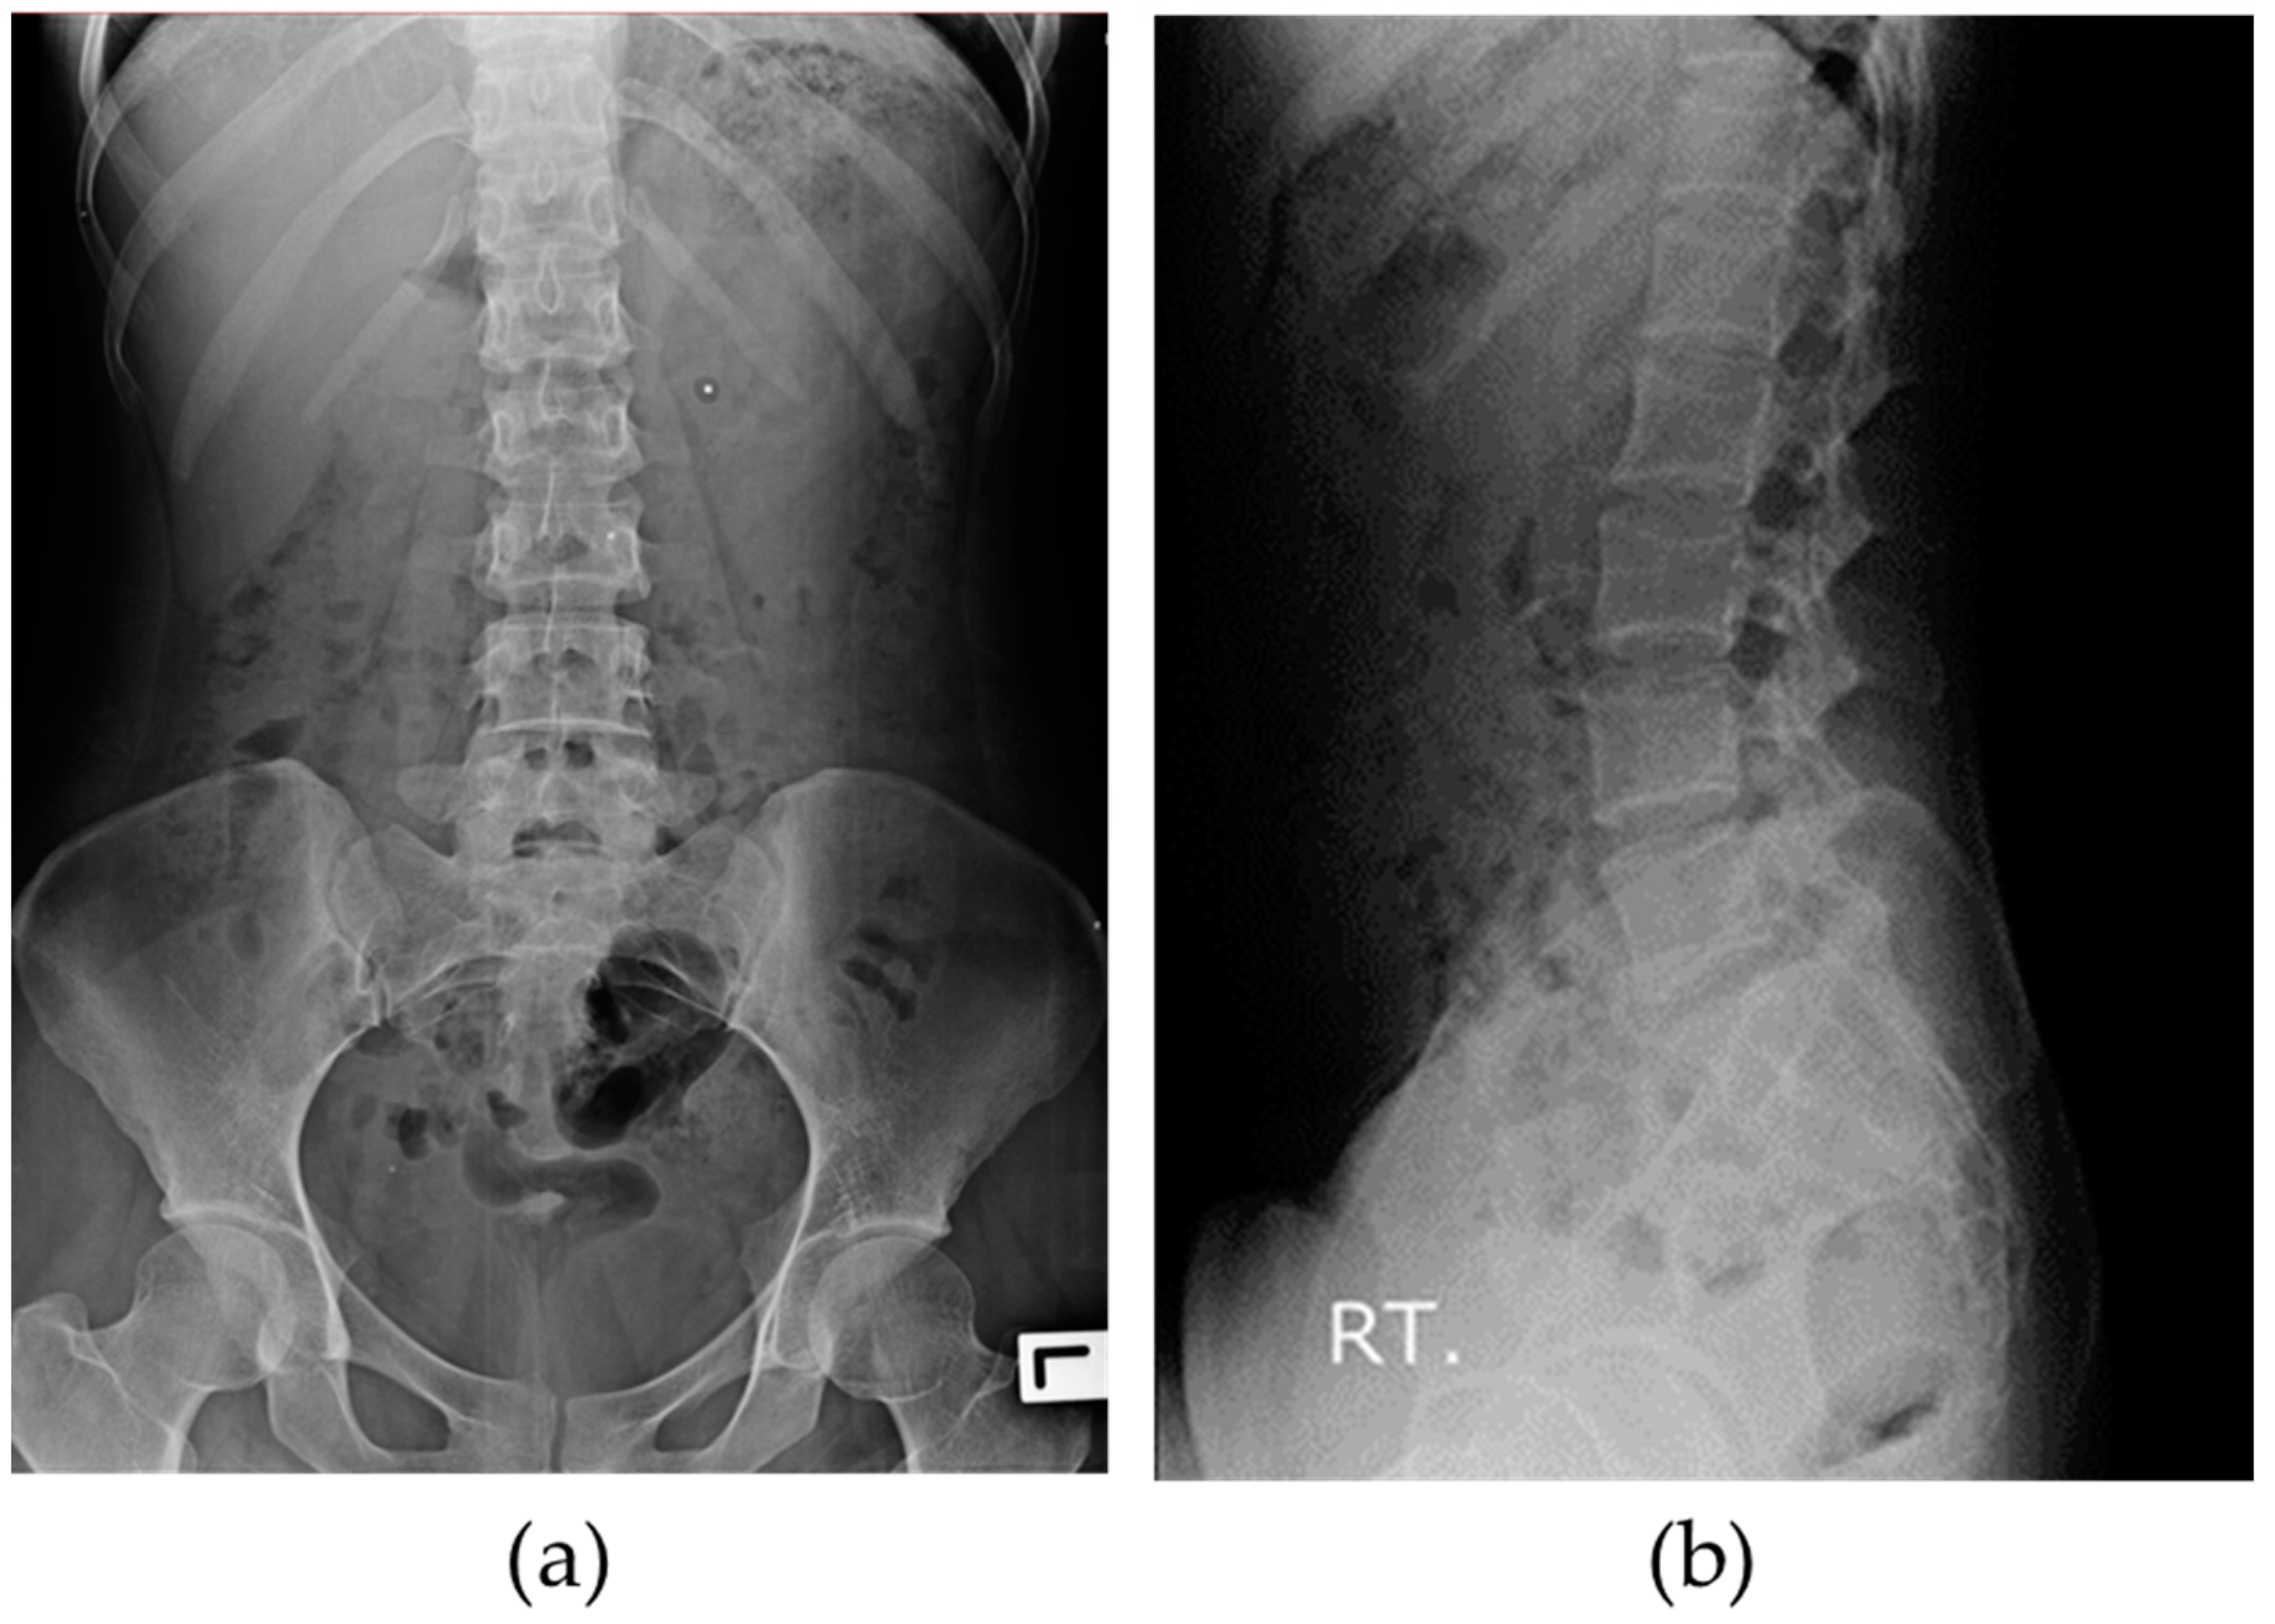

2.1. BUU-LSPINE

2.2. Ground Truth Data